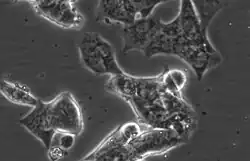

Representative phase-contrast image of LAPC4 cells. 32X magnification.

LAPC4 cells are a cell line of human prostate cancer commonly used in the field of oncology. The tissue was harvested from the lymph node metastasis of a male patient with hormone refractory prostate cancer which was then xenografted into SCID mice and later harvested and plated on tissue culture dishes, where it can be propagated as an immortalized prostate cancer cell line.[1][2][3]